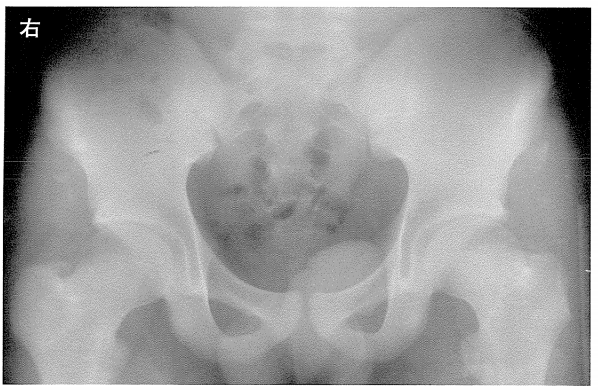

問題224

15歳の男子。陸上100m走でスターートと同時に左股関節に疼痛が生じた。単純エックス線写真(別冊No.4)を別に示す。膝屈曲位で制限される股関節運動はどれか。

1. 屈曲・外転・外旋

2. 屈曲・内転・内旋

3. 伸展・外転・外旋

4. 伸展・内転・内旋

答え.1